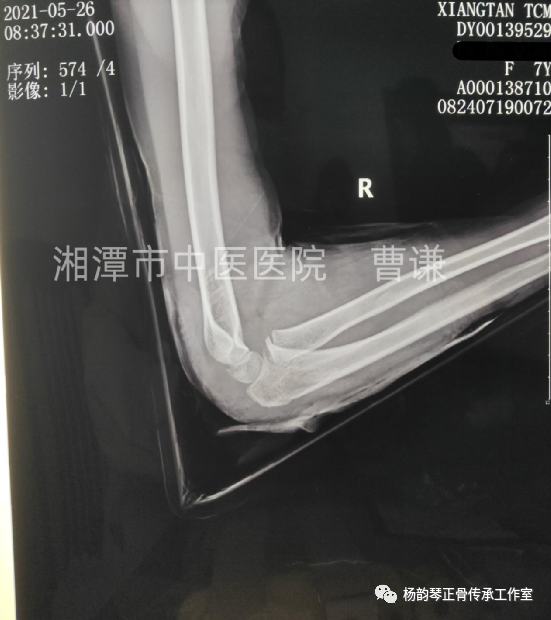

辅助检查:X线片:右尺骨近端骨折,右桡骨头脱位。

孟氏骨折特别容易漏诊的就是桡骨头脱位,此患者从侧位片上看可以看到桡骨近端纵轴线没有通过肱骨小头中心,提示肱桡关节匹配不良,桡骨头脱位。除非直接暴力导致尺骨骨折,一般单纯尺骨骨折比较少见,临床上看到尺骨骨折就必须密切关注肱桡关节匹配情况,桡骨头脱位后可能自动还纳,若此时忽略对桡骨头的固定,可能发生再脱位。所以即使X线片仅见骨折而无脱位,一般最好也按孟氏骨折来处理,避免漏诊。